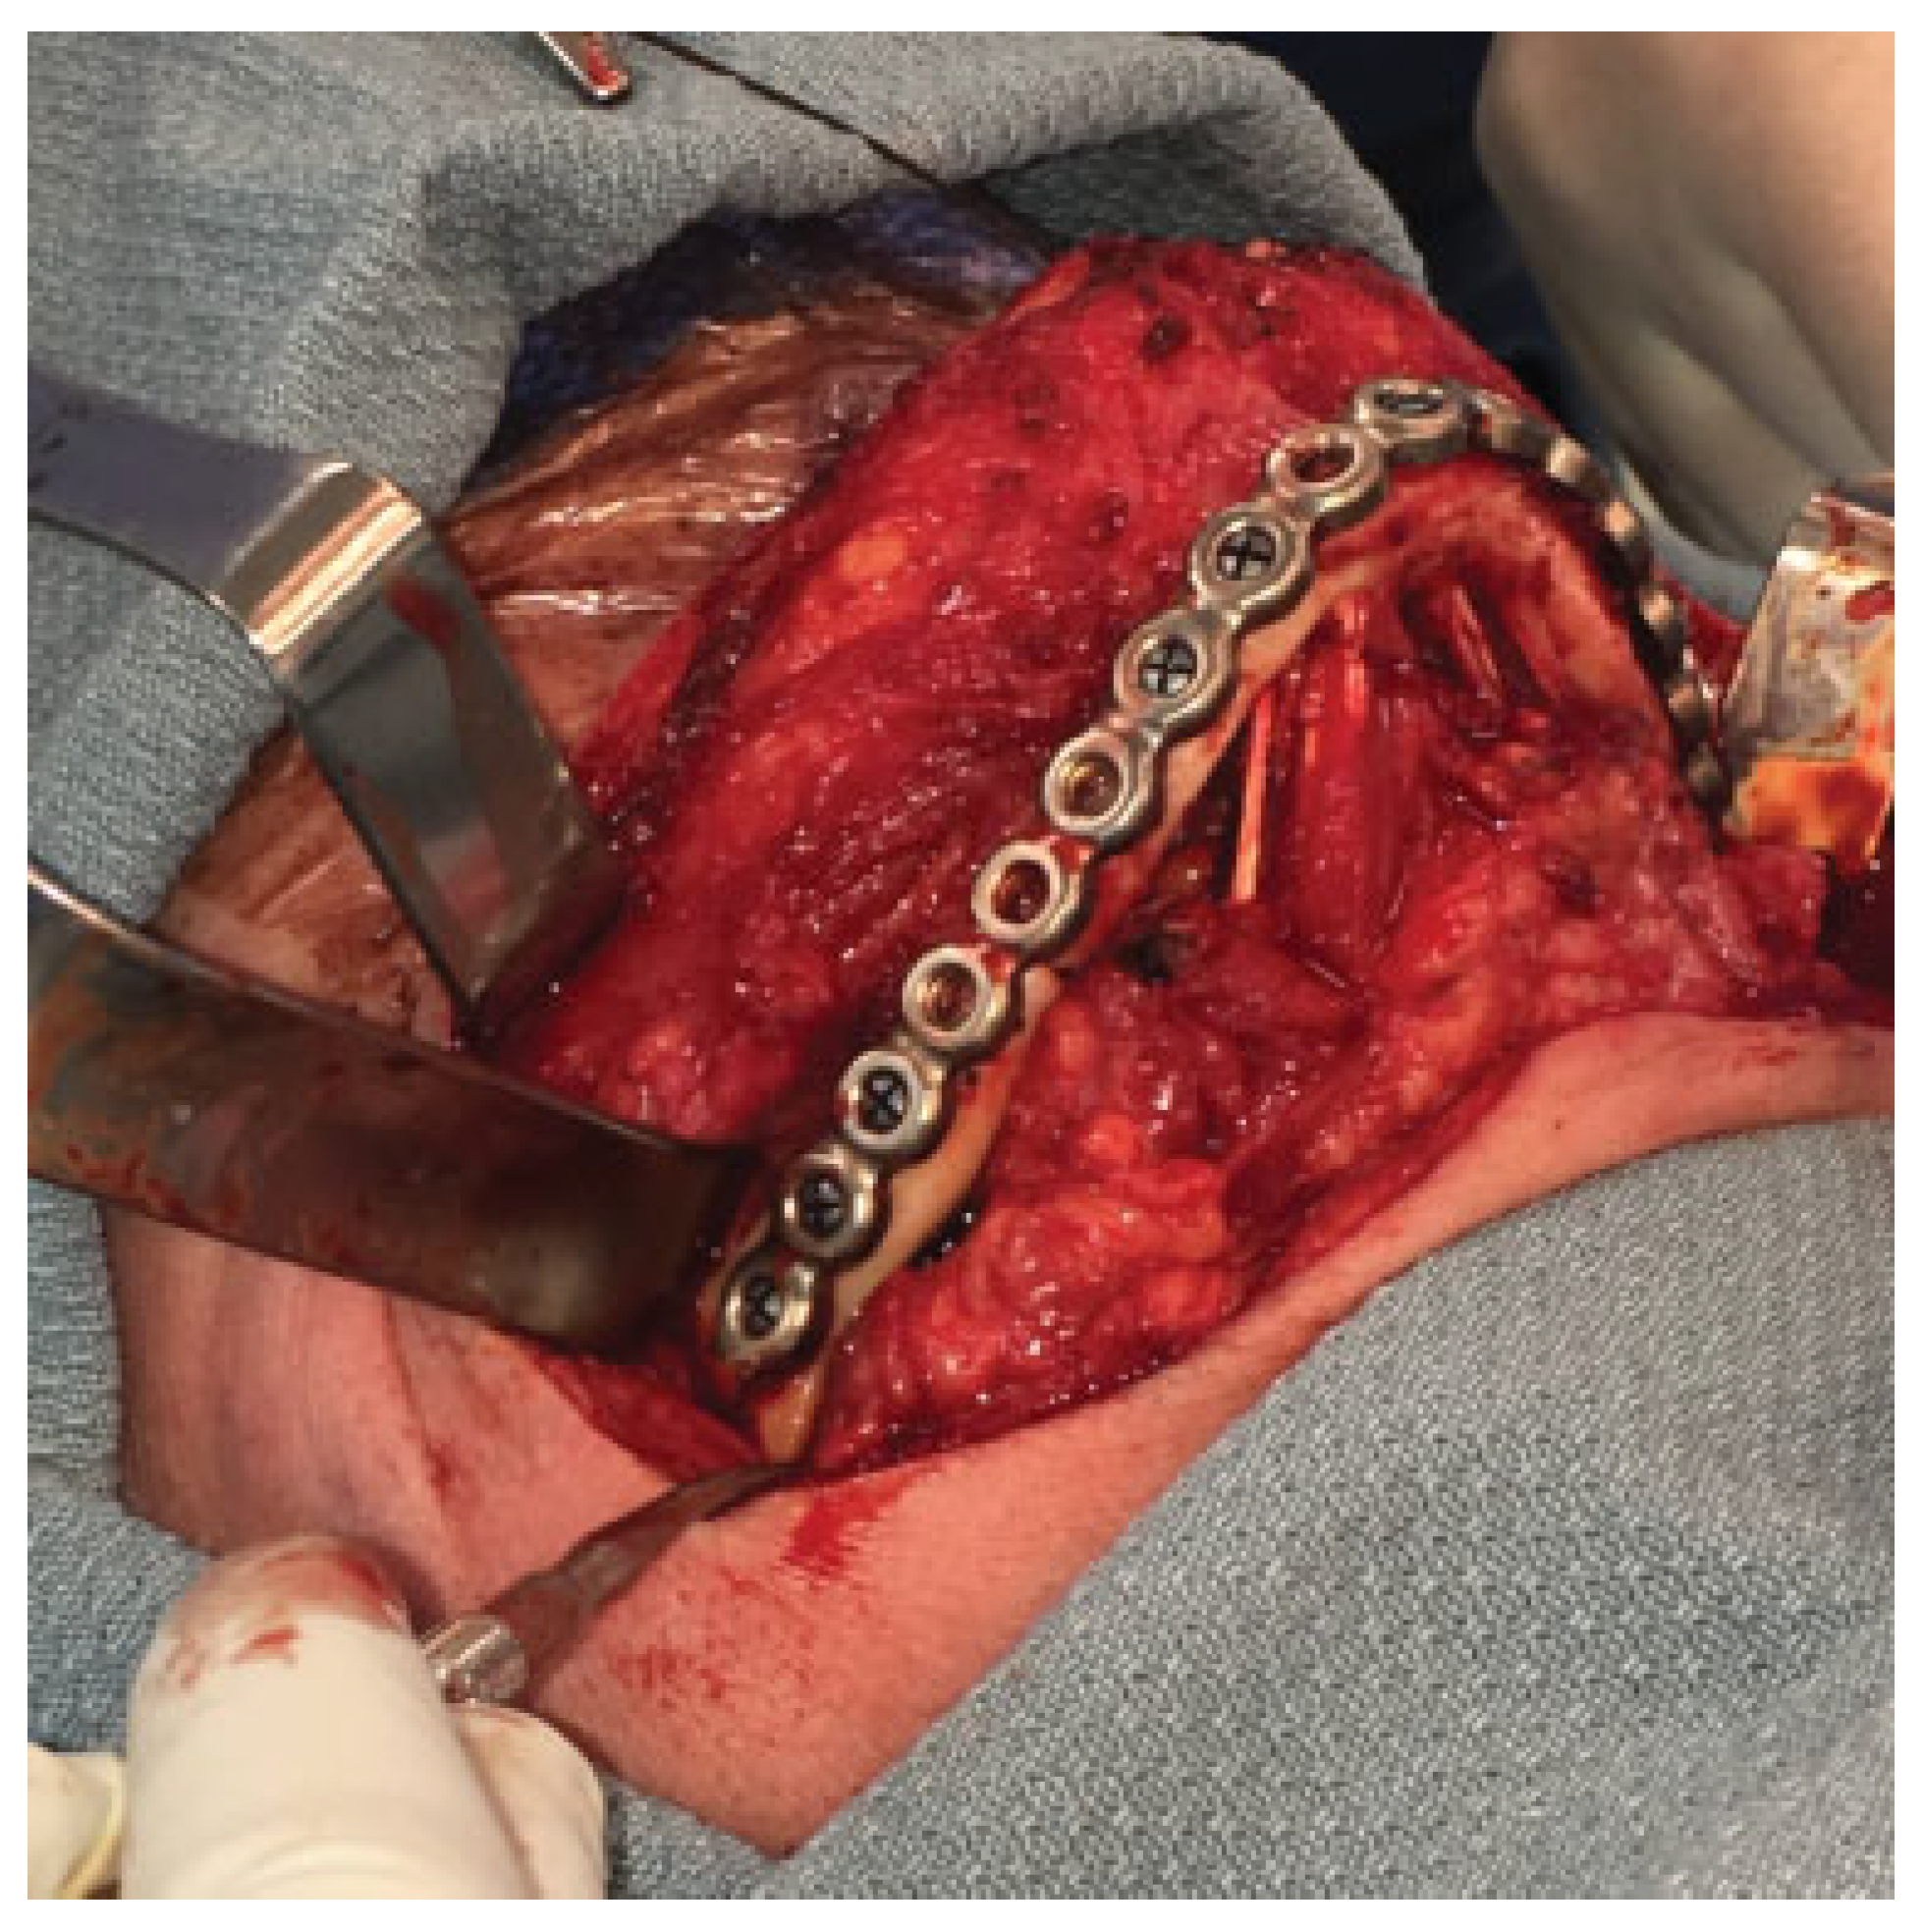

An extended submandibular approach was used and the mandible was exposed from angle to angle. The prebent plate was utilized to aid in the alignment of the segments and multiple bicortical locking screws were used (Figure 5). Multiple small fragments of bone were removed, the fracture sites were then debrided, and allograft (DBX Demineralized Bone Matrix–Musculoskeletal Transplant Foundation, Edison, NJ) was placed into the fracture sites. Layered closure was then performed (Figure 6). A postoperative panoramic radiograph showed good reduction of the fractures, intact hardware, and good plate adaptation (Figure 7). The patient was discharged on postoperative day 1. She was seen at 2 weeks and 6 months postoperatively and her injury healed well without complications.

Figure 5. Intraoperative photo of prebent hardware fixation.